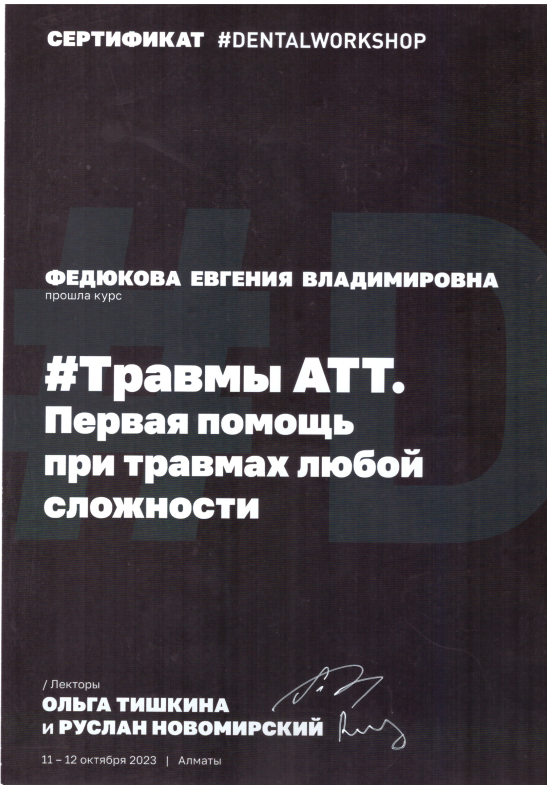

Федюкова Евгения Владимировна